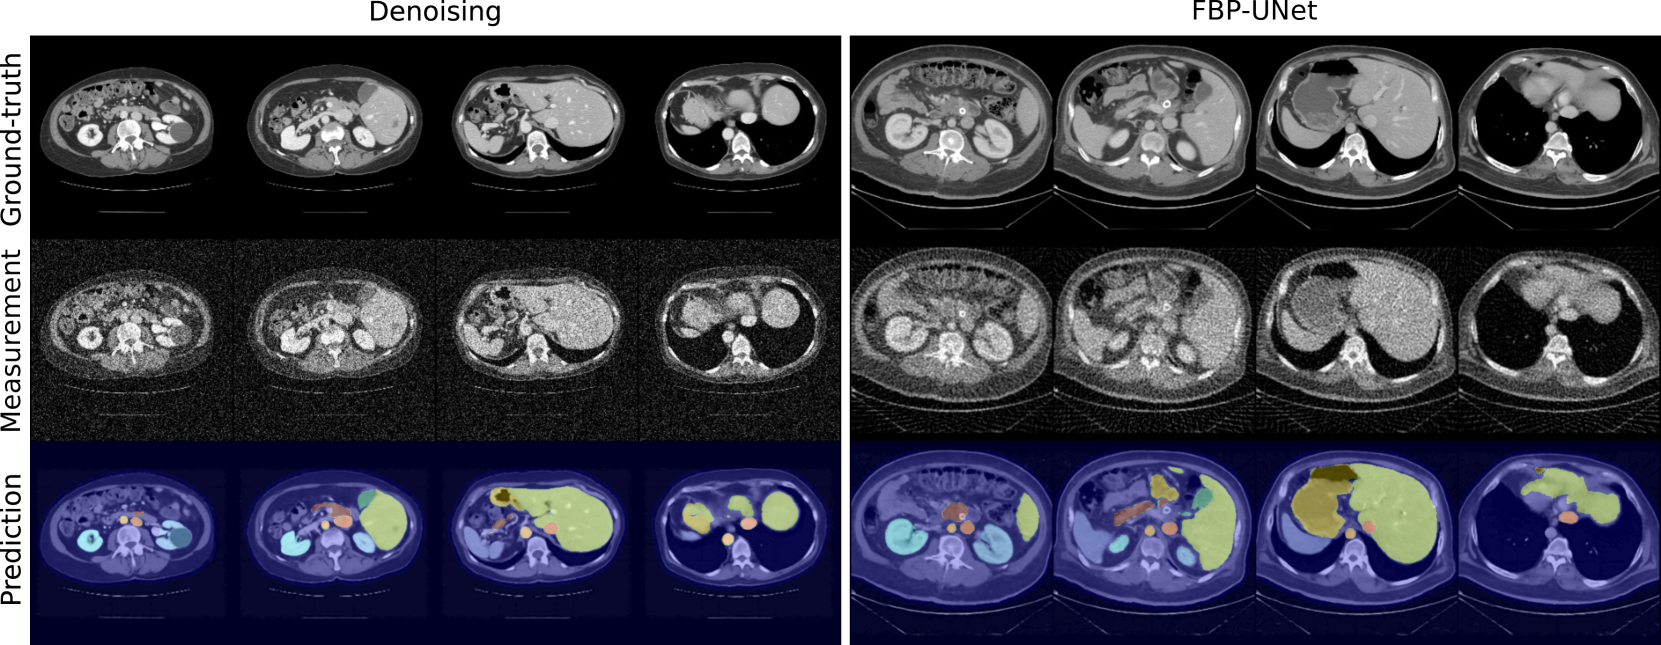

Refer to caption

(a) TotalSegmentator.

(b) FLARE23.

Figure 1: Example calibration data: ground-truth, measurement, and segmented predictions for both tasks and datasets.

Since sem-CRC𝑠𝑒𝑚-CRC{sem\text{-}{\text{CRC}}}italic_s italic_e italic_m - roman_CRC relies on a fixed segmentation model, we evaluate predictions in terms of mean structure-wise F1 score between the segmented outputs and the ground-truth annotations over 200 random volumes. For the TotalSegmentator dataset, we obtain 0.85±0.07plus-or-minus0.850.070.85\pm 0.070.85 ± 0.07 and 0.83±0.08plus-or-minus0.830.080.83\pm 0.080.83 ± 0.08 for denoising and FBP-UNet, respectively; and, equivalently, 0.88±0.06plus-or-minus0.880.060.88\pm 0.060.88 ± 0.06 and 0.87±0.07plus-or-minus0.870.070.87\pm 0.070.87 ± 0.07 for the FLARE23 dataset. Although we see a slight drop in performance compared to the metrics reported in [17], these results confirm predictions are of reasonable quality for segmentation, and we include some examples in Fig. 1.